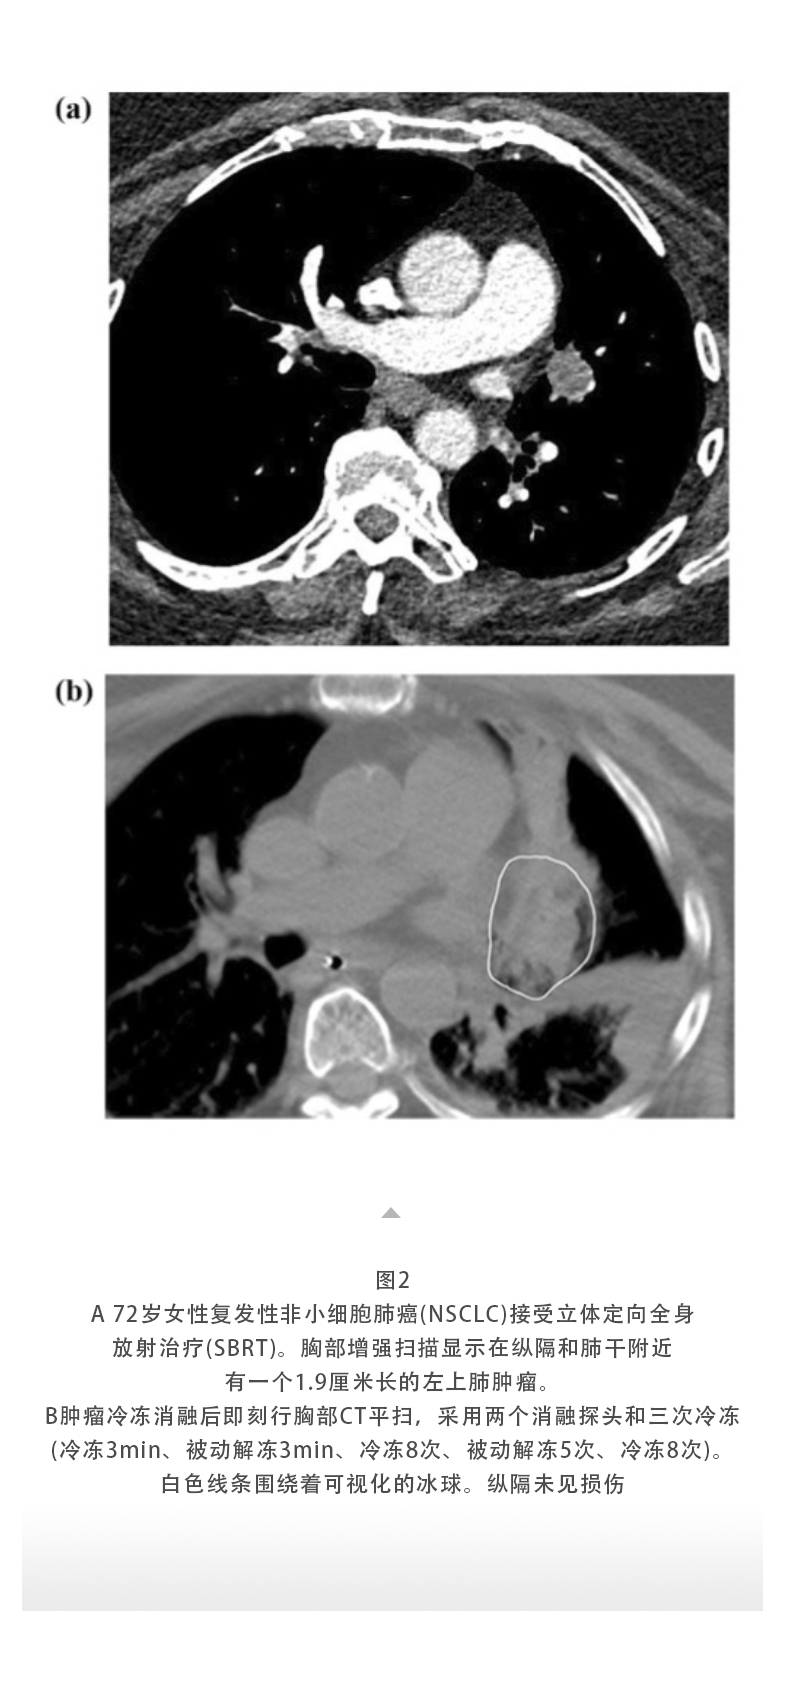

上一页:【HYGEA·科研资讯】冷冻消融治疗肺癌